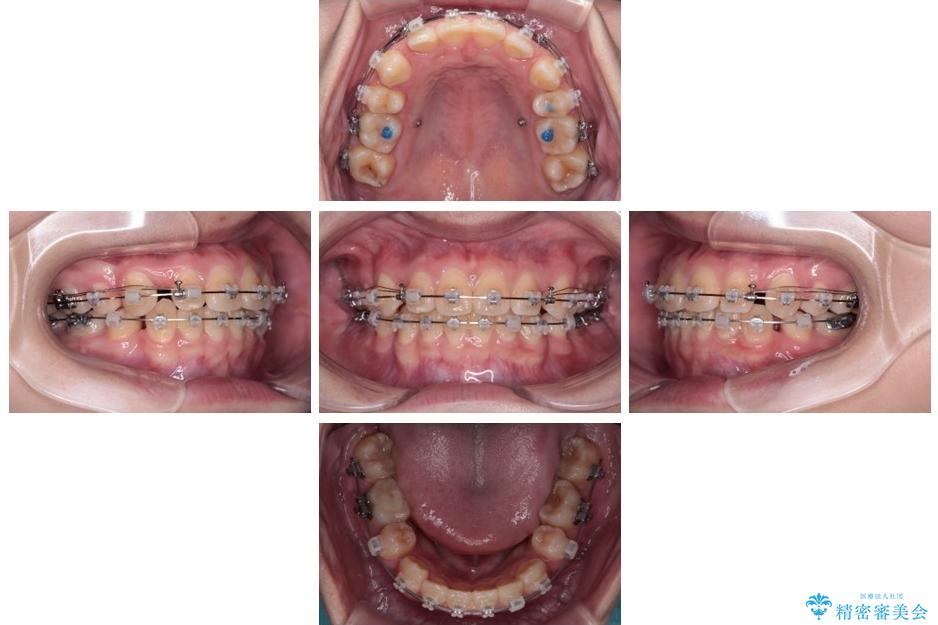

治療途中

• 転勤でも安心して治療継続 抜歯スペース閉鎖と深い噛み合わせ改善のワイヤー矯正 治療途中画像